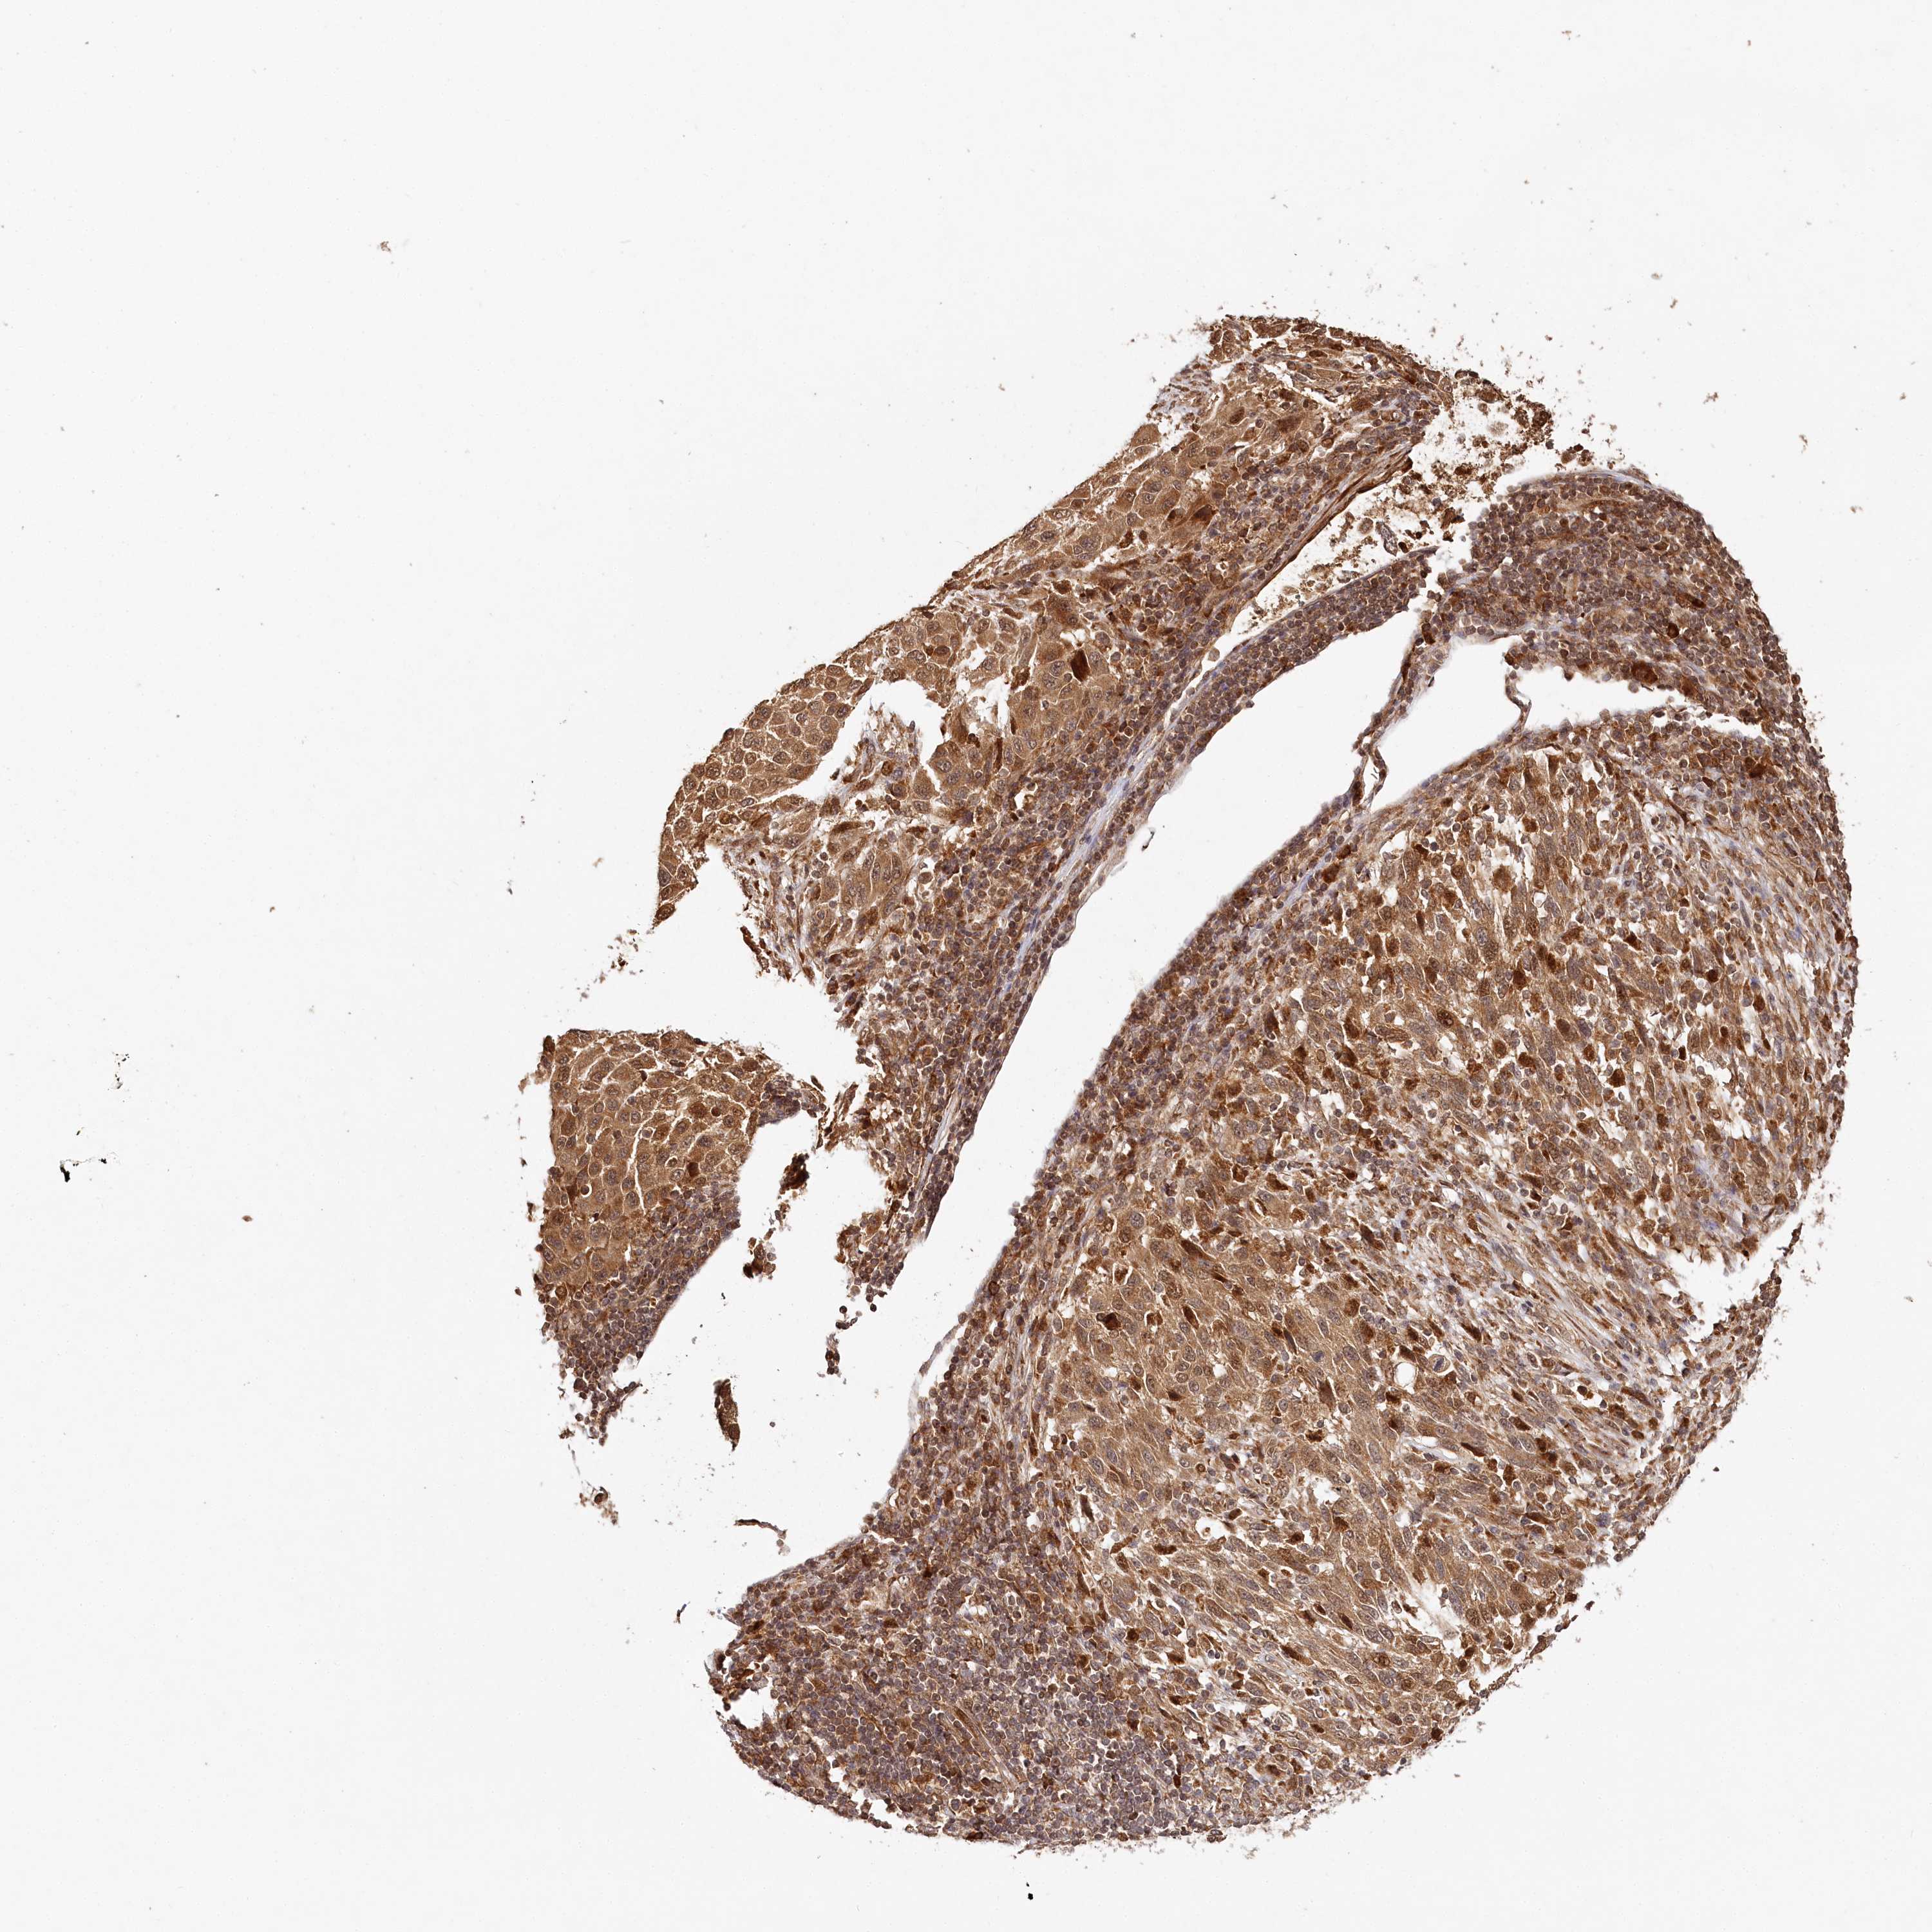

MELANOMA - Protein expressioni

A mouse-over function shows sample information and annotation data. Click on an image to view it in a full screen mode. Samples can be filtered based on level of antibody staining by selecting one or several of the following categories: high, medium, low and not detected. The assay and annotation is described here.

Note that samples used for immunohistochemistry by the Human Protein Atlas do not correspond to samples in the TCGA dataset.

Antibody stainingi

Antibody staining in the annotated cell types in the current human tissue is reported as not detected, low, medium, or high, based on conventional immunohistochemistry profiling in selected tissues. This score is based on the combination of the staining intensity and fraction of stained cells.

Each image is clickable and will lead to virtual microscopy that enables deeper exploration of all samples and also displays staining intensity scores, fraction scores and subcellular localization as well as patient and tissue information for each sample.

Antibody CAB037021

Staining

High

Medium

Low

Not detected

Intensity

Strong

Moderate

Weak

Negative

Quantity

>75%

75%-25%

<25%

None

Location

Nuclear

Cytoplasmic/membranous

Cytoplasmic/membranous,nuclear

Malignant melanoma, NOS